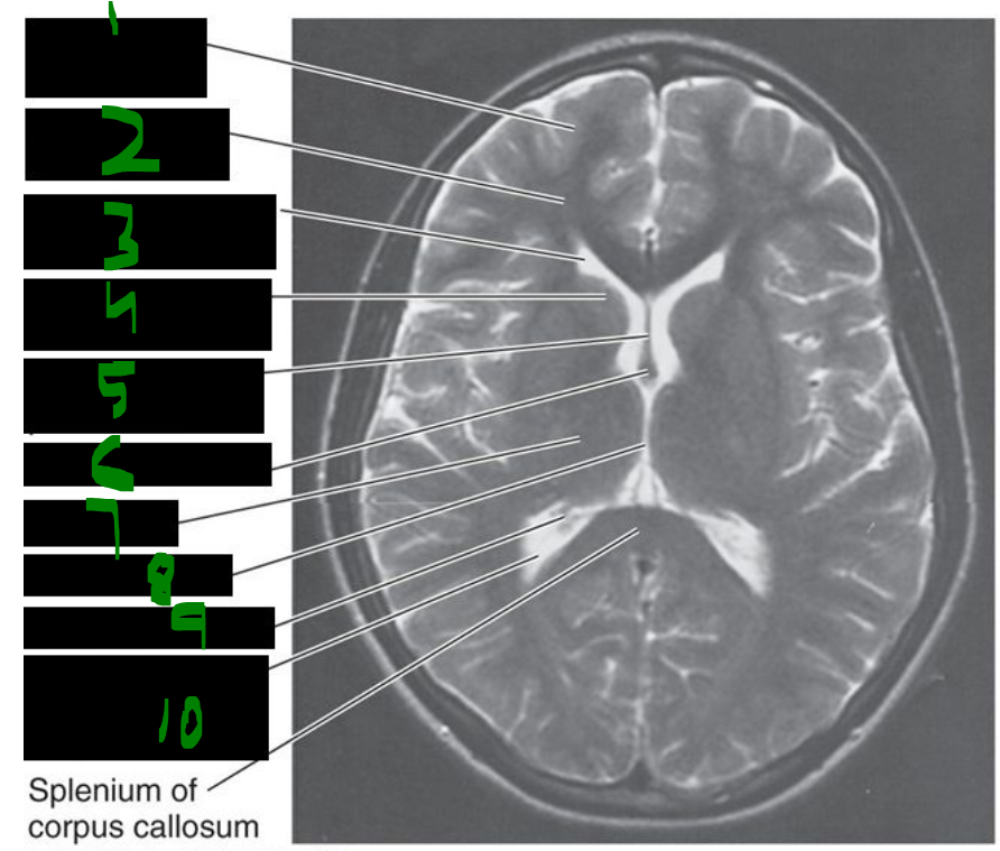

69

The internal carotid artery is a branch of the ______ ______ artery, enters the cranial cavity through the ______ ______, passes through the ______ ______, and primarily supplies the ______, ______, and ______.

common carotid, carotid canal, cavernous sinus, orbit, eye, brain

70

The vertebral artery is the first branch of the ______ artery, travels through the transverse foramina of ______ to ______, enters the ______ ______, and joins the opposite vertebral artery to form the ______ artery.

subclavian, C6, C1, foramen magnum, basilar

71

what is the main blood supply of the brain?

______ ______ a.

______ a.